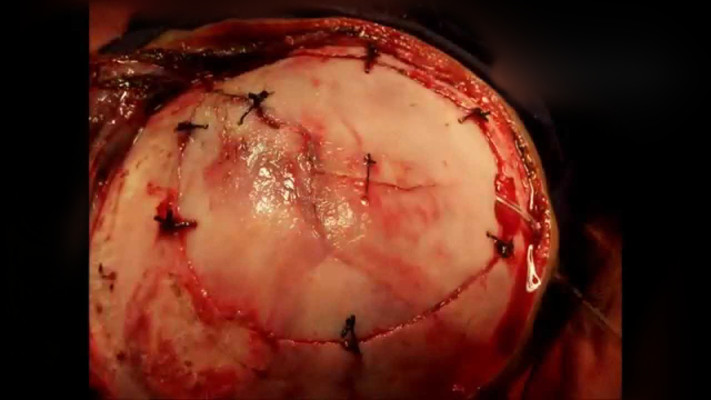

顱內血腫圖片

硬膜下血腫 (50)

硬膜下血腫 (6)

硬膜下血腫 (39)